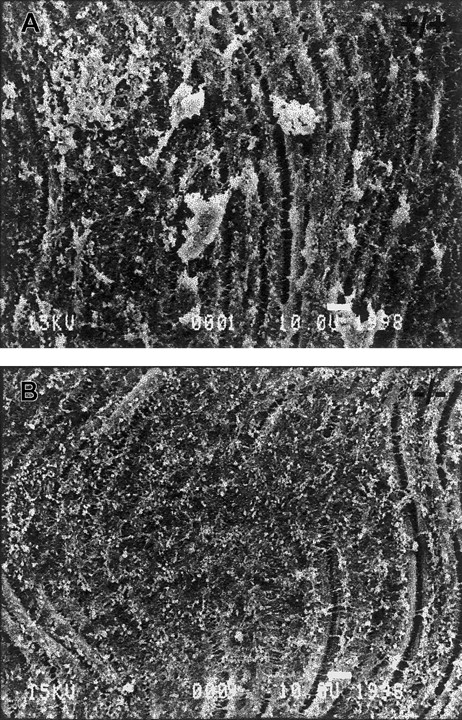

To better examine the interaction of platelets with the exposed subendothelium we analyzed denuded arteries by TEM. By this method we observed numerous aggregates in wild-type mice that involved a layer of flattened and activated platelets adhering to the subendothelium, covered by layers of closely adherent platelets (Figure2A). TSP2-null subendothelia mostly lacked such aggregates, and only occasional small aggregates, consisting of loosely organized platelets and displaying minimal cell-cell interactions, were present (Figure 2B). The lack of intimacy in the interactions of TSP2-null platelets was in marked contrast to the extensive and close interactions displayed by wild-type cells. Consistent with our findings with SEM, numerous flattened platelets adhering to the subendothelium could be observed in TSP2-null mice. These findings suggest that platelet aggregation is compromised in TSP2-null mice and provide a basis for the bleeding diathesis in these animals. However, the denudation experiments do not distinguish between a subendothelial matrix abnormality and an intrinsic platelet defect. We proceeded to examine the latter possibility by analyzing platelet function ex vivo.

TEM images of platelet aggregates.

Representative TEM images of denuded carotid artery subendothelium 10 minutes following injury. A large platelet aggregate with several layers of intimately associated platelets can be seen in wild-type mice (A). A glancing section of the internal elastic lamina is seen as a white band. In contrast, a small aggregate of platelets displaying minimal interactions can be seen in TSP2-null mice (B). A total of 5 mice per genotype was analyzed. Bar represents 1 μm.